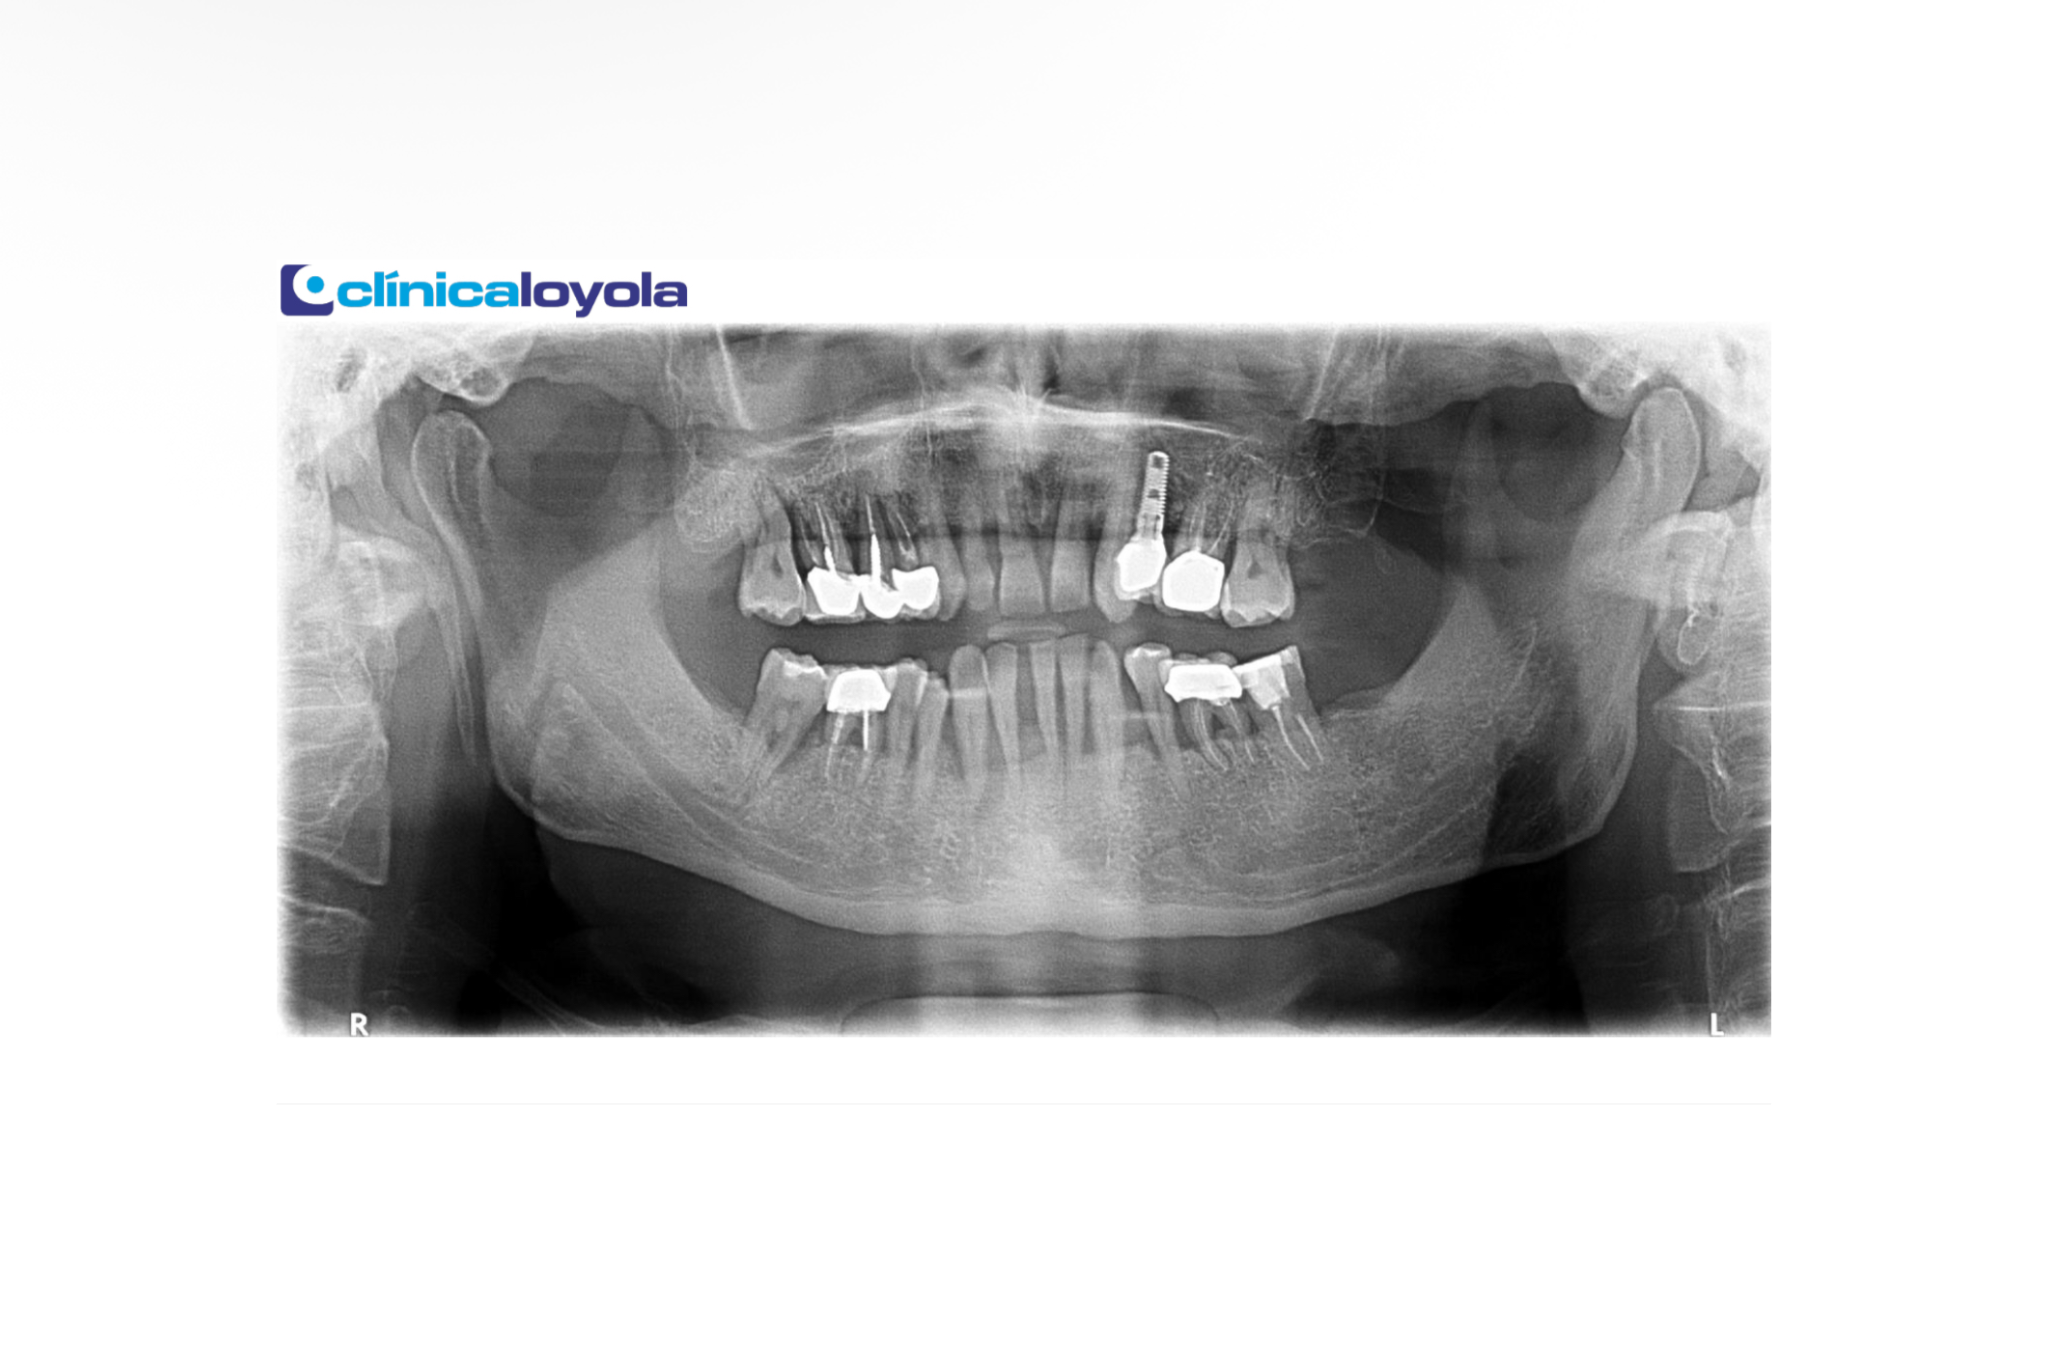

BONE REGENERATION

They employ the latest technology for bone regeneration, allowing them to offer a guarantee for all their treatments.